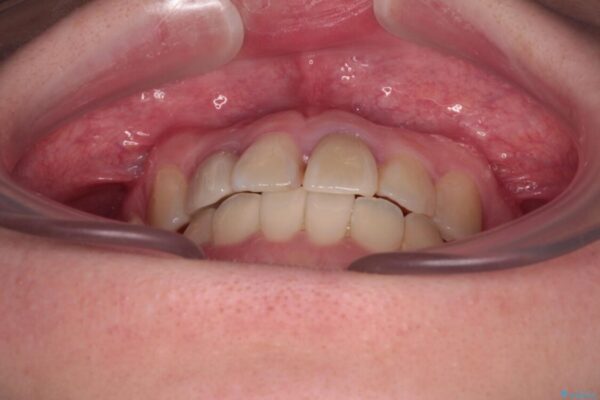

治療前

• 虫歯治療ついでに歯並びの後戻りを改善 インビザラインによる矯正治療 治療前画像